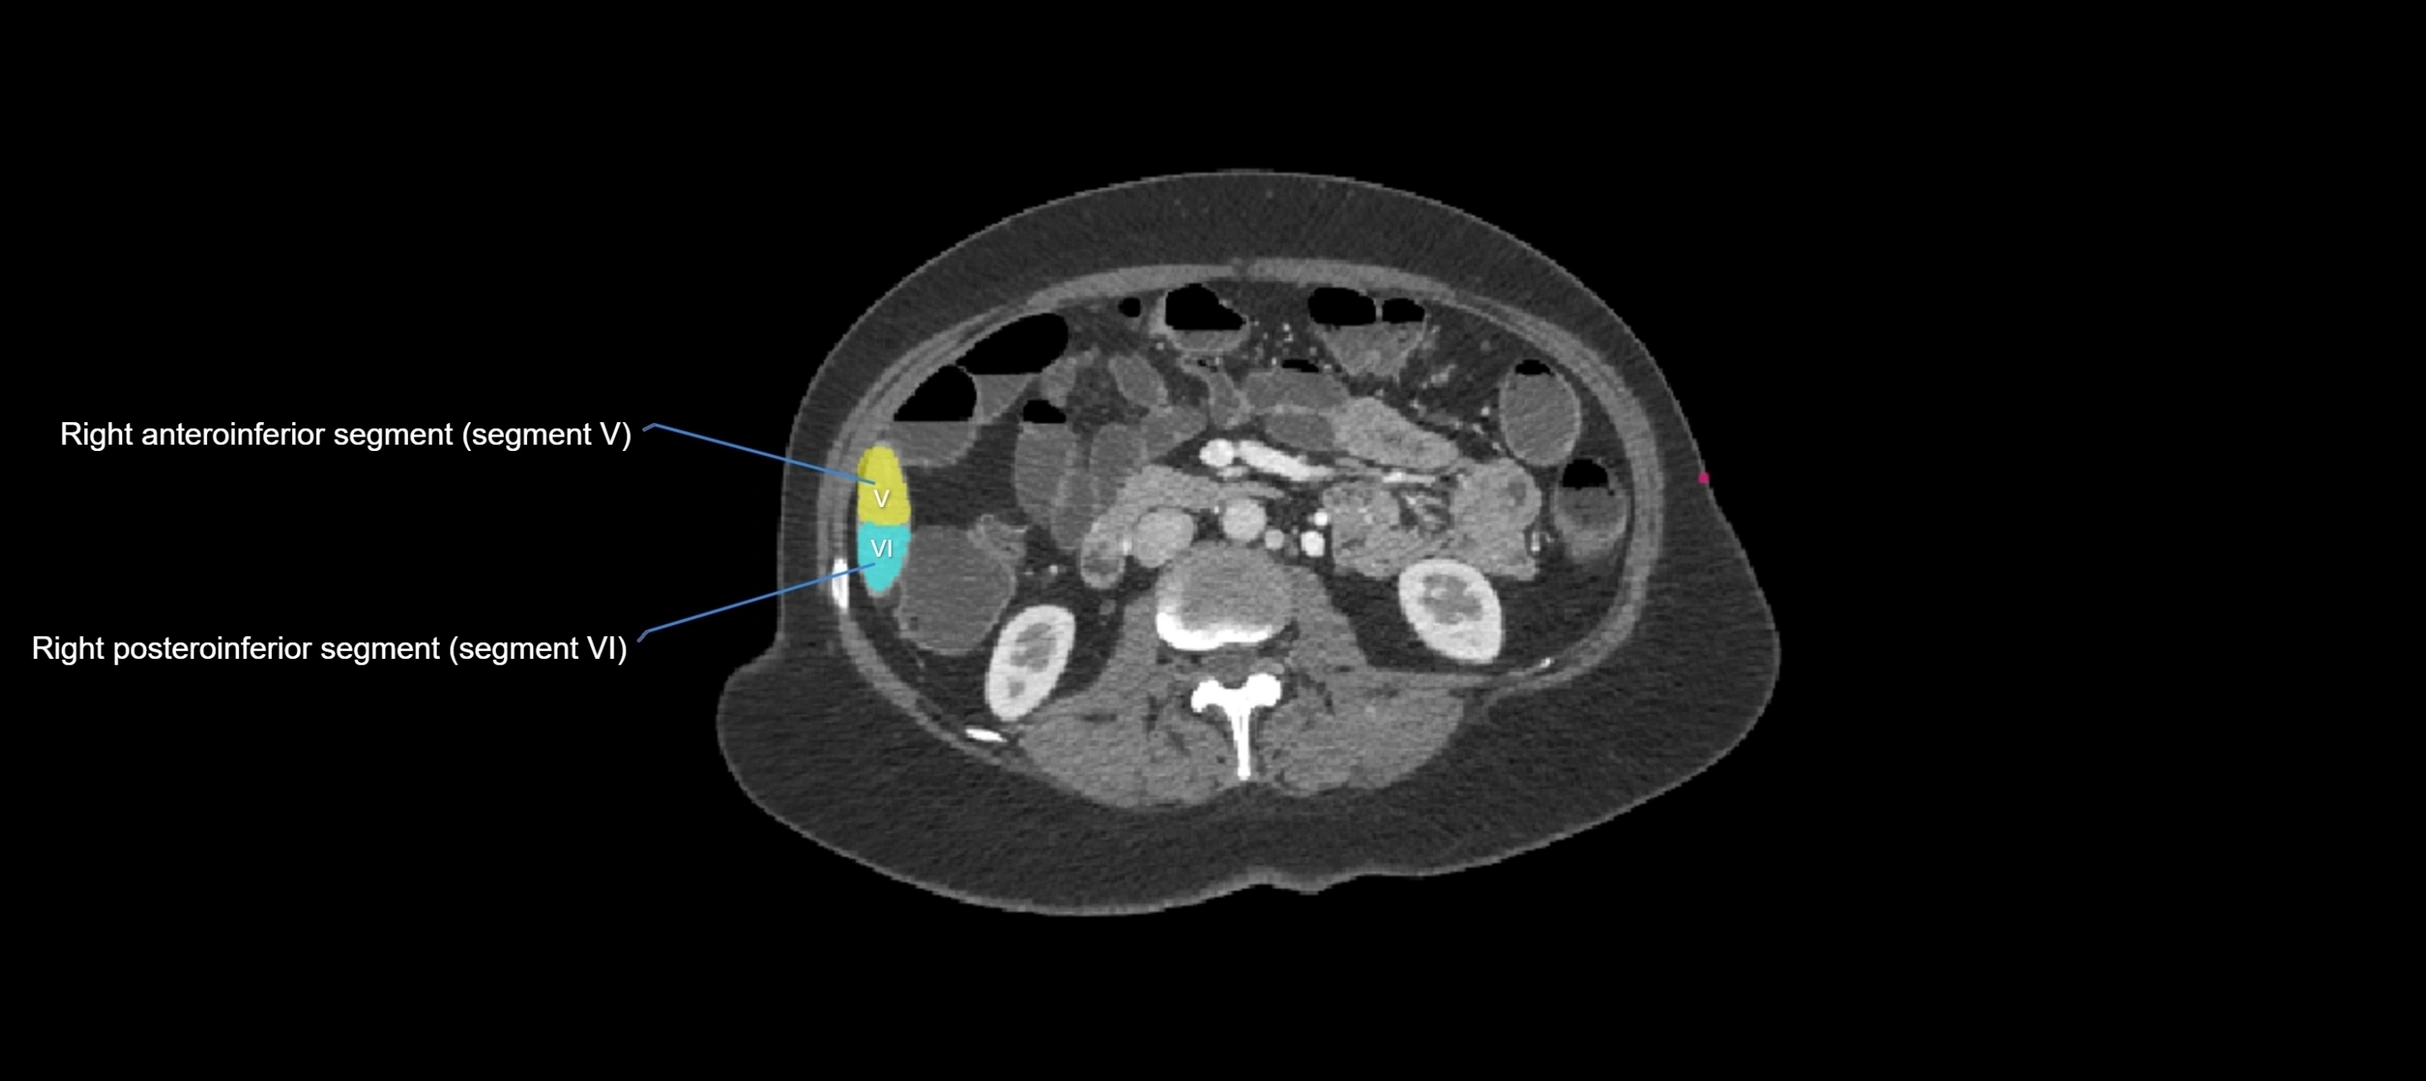

CT Image

image